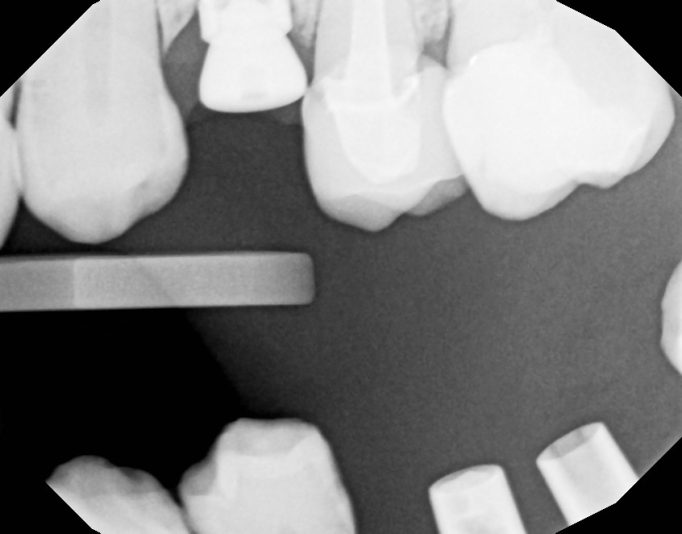

I placed this implant 8 months ago. It was immediate placement. I did the uncovery today. The pre op radiograph shows some loose bone graft. I didn’t really notice anything off upon flapping . ISQ 77. Is it something I should be concerned about?

So I suspect the implant was placed in cortical bone at the top and the lack of blood supply caused this die off. It could also be the lack of KT thickness. This is why I routinely place my implant 2mm subcrestal. At this point I don’t think there’s anything that can be done. It’ll be ok, just something to remember for next time.

It doesn’t look like it will be a problem. Some of the graft turns over into natural bone–but some (like the graft stuck in soft tissue shown above your implant) will not turn over. It’s ok.